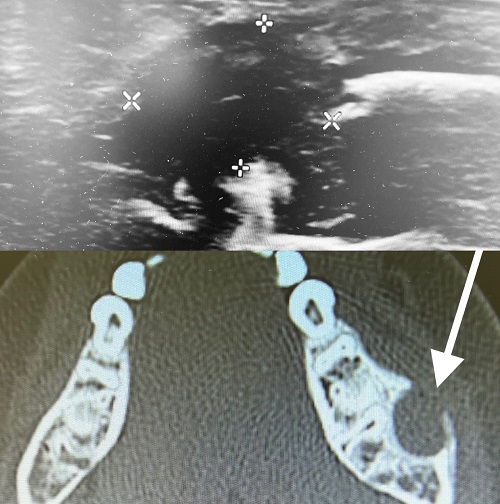

Se presenta un niño de 7 años que consulta por presentar inflamación repentina y dolorosa en la rama mandibular izquierda el día anterior (Fig. 1). Las características clínicas apoyan el diagnóstico de flemón dentario y se trata con amoxicilina-clavulánico e ibuprofeno a las dosis habituales. A la semana presenta resolución del proceso. En la revisión odontopediátrica no se detectan caries ni otras patologías orales. Consulta de nuevo al mes por presentar recidiva de la inflamación en la misma zona (Fig. 1). Una nueva exploración odontológica tampoco detecta patología dental. Se realiza una ortopantomografía que es normal. Dada la recurrencia, se indica una ecografía que muestra una colección heterogénea en rama mandibular de 11 mm (Fig. 2) y el estudio se completa con una tomografía axial computarizada que muestra una lesión quística de 10 mm bien definida en la rama mandibular, que rompe la cortical externa (Fig. 2). Se diagnostica probable QO. Es intervenido quirúrgicamente y la biopsia confirma el diagnóstico de QO: quiste revestido por epitelio pavimentoso sin queratinización, que presenta en el corion subyacente un infiltrado inflamatorio crónico linfohistiocitario, sin rasgos displásicos ni de malignidad; cultivos bacterianos y fúngicos negativos. Presenta buena evolución, sin complicaciones ni recidivas a los 9 meses de la intervención.

| Figura 2. Quiste odontogénico. Imagen ecográfica del quiste (arriba, marcas). Tomografía axial computarizada, rompiendo la cortical (abajo, flecha) |

El diagnóstico del quiste, antes de que aparezcan los síntomas, suele ser casual al realizar una radiografía de la zona por otro motivo1,2,5,6. En nuestro caso, se realizó una ortopantomografía al recidivar el flemón en la misma localización, tras haber desaparecido con el tratamiento habitual. La imagen más habitual es una lesión radiolucente redondeada u ovoidea bien definida1,2,6, que no presentó nuestro caso. Al no hallarse ninguna patología causal en la exploración odontopediátrica, se realizaron una ecografía y una tomografía axial computarizada para obtener el diagnóstico de presunción (Fig. 2).

La evolución del QO suele ser lenta1,2,3,5, pero nuestro caso presentó un comportamiento más agresivo, creciendo con rapidez y rompiendo la cortical ósea externa de forma prematura. La tendencia a destruir el hueso adyacente hace que los QO requieran tratamiento, generalmente endodóntico; en ocasiones, con extracción del diente afectado1-3,5,7. Nuestro caso mostró un comportamiento más agresivo y precisó cirugía, con escisión completa de la lesión por enucleación, conservando el diente.